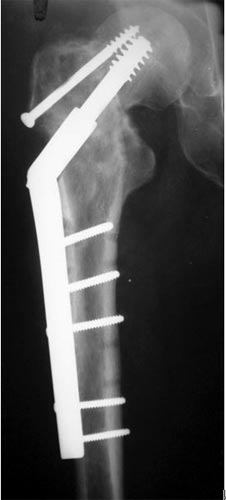

以上图片为三位患者的X线片,显示股骨粗隆下骨折、骨不连,内固定已经失败。

主要采用股骨重建髓内钉获得良好早期的稳定性,为骨愈合创造条件,